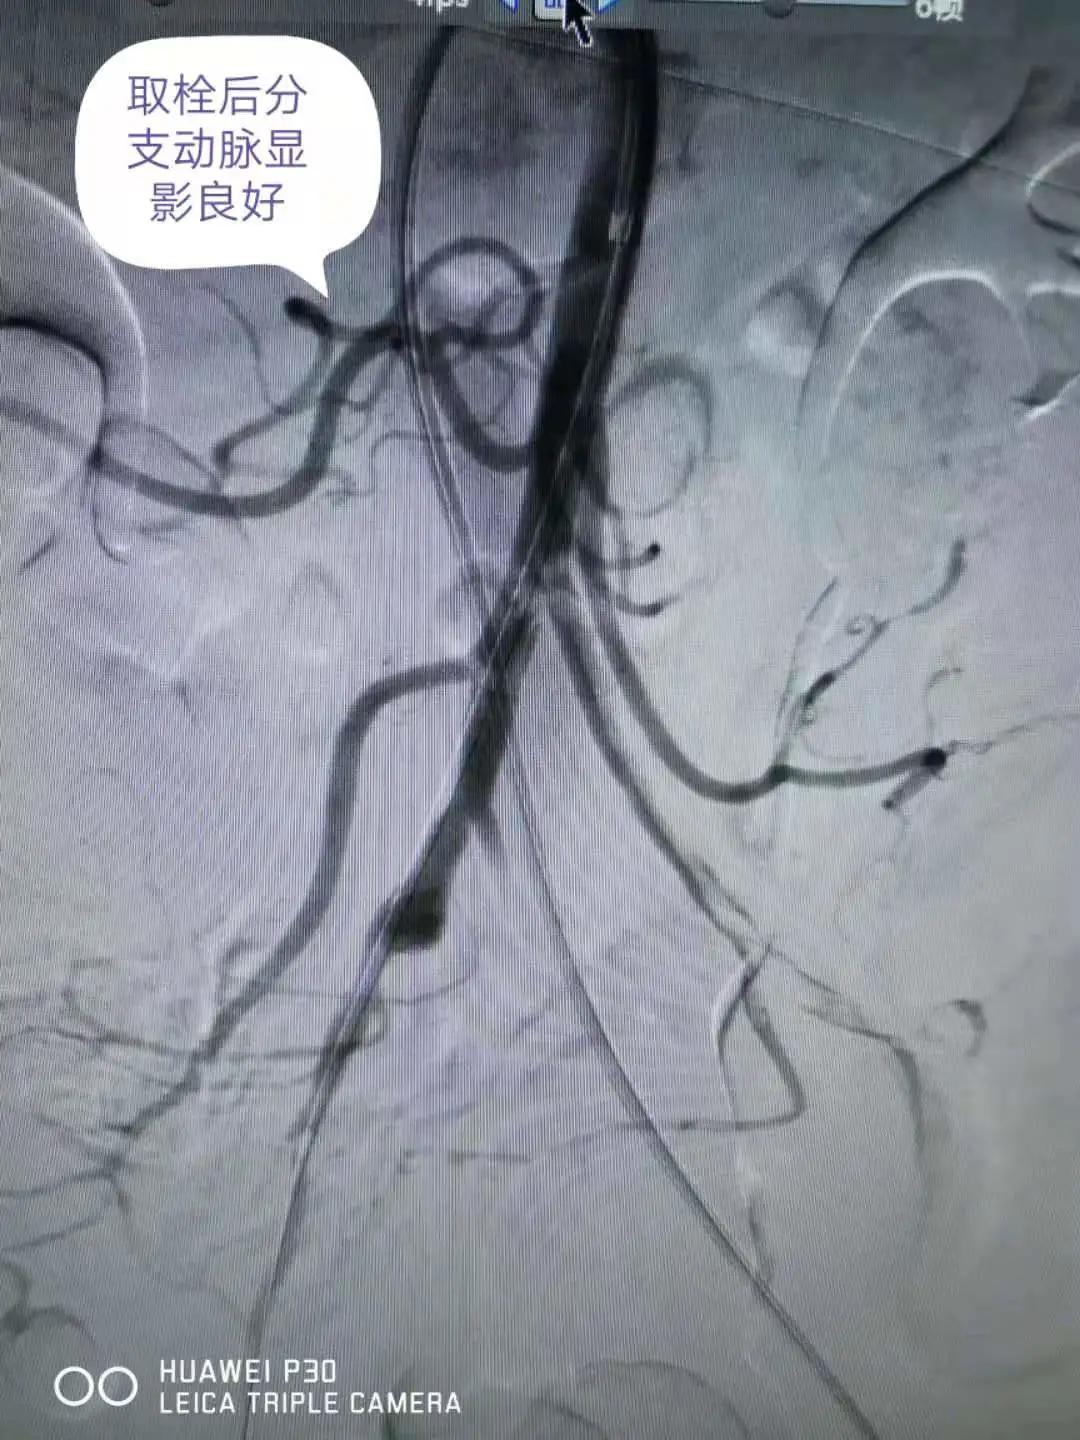

两名大夫在落实疫情防控要求的同时,最大程度地缩短准备时间,争取以介入治疗的方式抢救肠道。经过几小时的奋战后,介入手术取出了肠系膜上动脉的大量血栓,老人的肠道功能保住了!

肠系膜动脉栓塞是由于血栓堵塞了肠道供血动脉,使肠袢发生急性缺血性坏死的疾病,是一种相对少见的急腹症。 早期由于阳性体征较少,临床上往往难于诊断,因此极易错失最佳手术治疗时机。 市中心医院血管外科团队以丰富的诊疗经验、精准的临床诊断、高效的术前流程,成功地救治了患者,让老人免于肠管切除的痛苦。